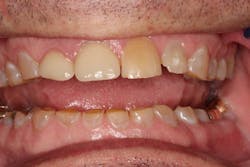

Founder Dr. Peter Dawson pioneered a systematic approach that allows any dentist to properly diagnose the root cause of wear issues. I knew that I could follow this approach to create a beautiful, highly functional, and long-lasting solution (figure 2).

Figure 2: After